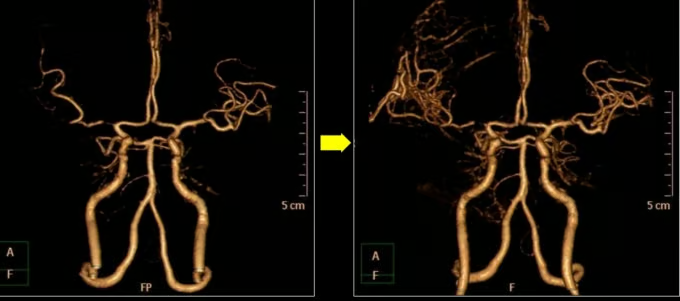

(사진 왼쪽부터) 막힌 뇌 혈관의 '우회로'를 뚫는 뇌혈관 문합술 전과 후 모습. /사진=에스포항병원

이런 뇌졸중 치료 분야에 '글로벌 강국'이 바로 한국이다. 뇌졸중 급성기 치료는 약물로 막힌 혈전(피떡)을 없애거나 기계적으로 흡입하고, 미세 스텐트를 이용해 빼내는 등 그 폭이 점차 확대되고 있다. 뇌혈관이 막혔는데, 함부로 손댔다가 터질지 모르는 '위험 부위'라면 해당 혈관을 다른 혈관과 이어 우회로를 만들기도 한다(뇌혈관 문합술). 뇌가 부어올라 정상적인 뇌세포를 압박할 땐, 두개골을 떼내어 압력을 낮춘 뒤 3D프린터로 해당 두개골을 '맞춤 재생'하기도 한다.